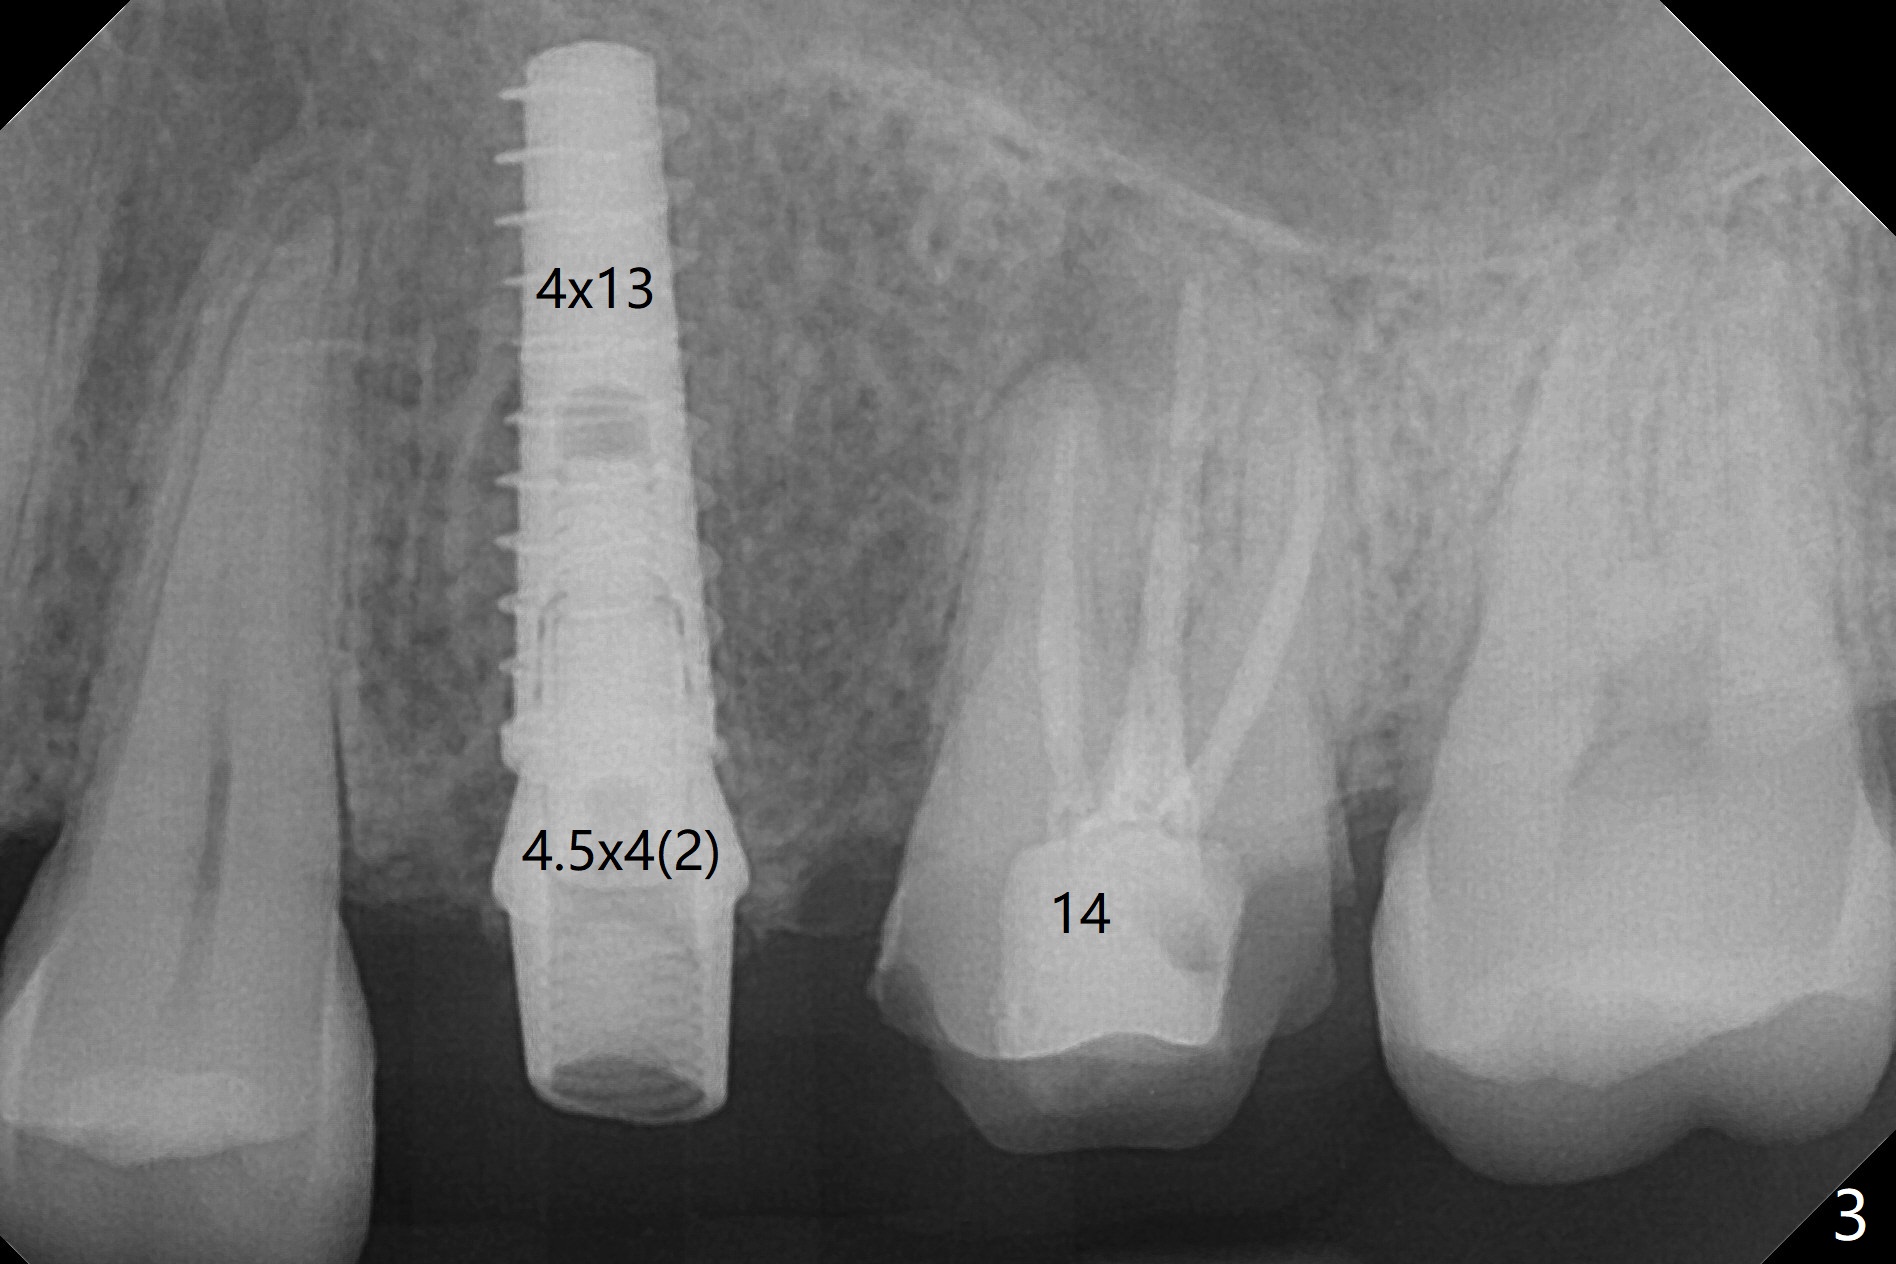

Due to misinterpretation of drill sequence, osteotomy is overprepared in depth (1.5 to 3 mm). When a 4x11 mm dummy implant is placed with > 50 Ncm (Fig.1,2), over placement is ignored. A 4x13 mm final implant is placed with fairly good torque, but it is deeper than expected. When it is backed up, primary stability is lost, in spite of placement of allograft in the osteotomy. Final torque is 15 Ncm. When a 4.5x4(2) mm abutment is placed, the underlying implant turns (Fig.3). A splinted provisional is fabricated at #13 and 14. RCT is retreated 5 months postop (Fig.4 *). An abutment with longer cuff is placed before impression (8.5 months postop, Fig.5). When the crowns of #13 and 14 are delivered, the former looks short and noncosmetic, although the gingiva will grow downward to close the gap (Fig.6). Ideally the gap should be closed with porcelain with overhang (Fig.7).